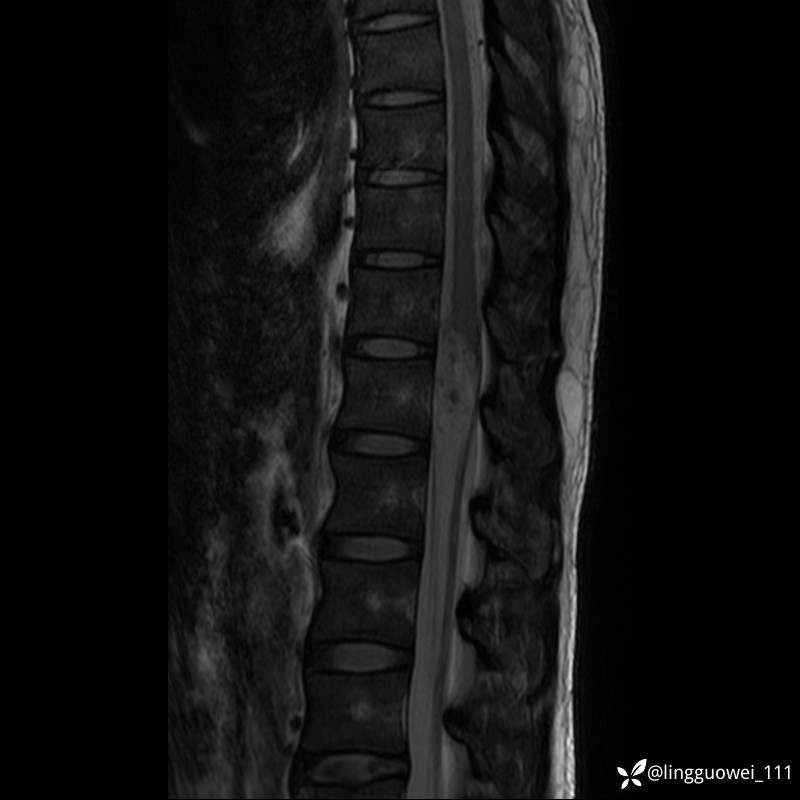

男,38岁,反复腰痛伴双腹股沟区痹痛半年,加重1月。

腰椎MR,注意脊髓异常信号,与伪影鉴别,一不小心就会漏诊

T1WI:

img